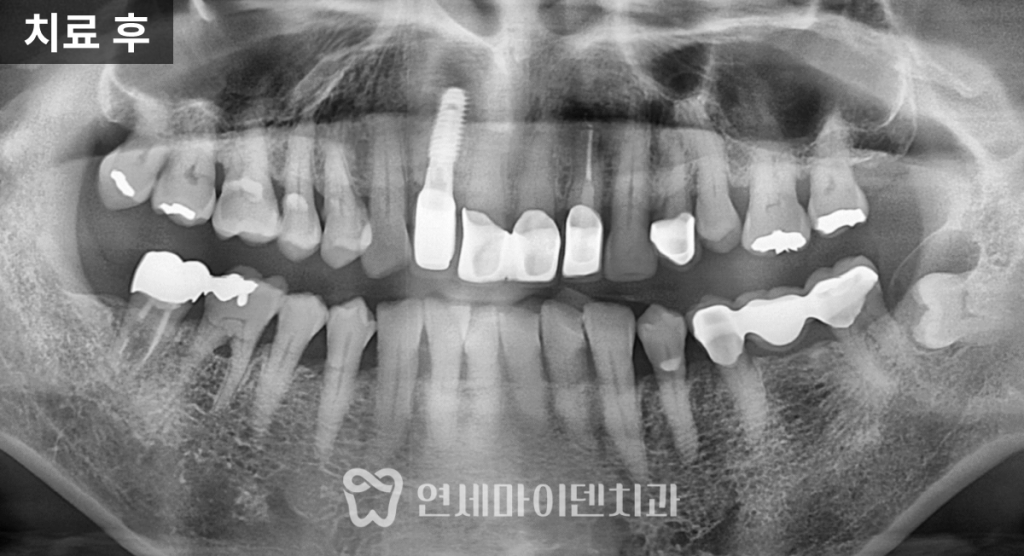

예후가 좋지 않은 앞니는

발치를 진행한 뒤

뼈이식을 동반한 임플란트를 식립했습니다.

3D CT를 활용해

임플란트 식립 각도와 위치를

정밀하게 계획했고,

초기 고정력을 안정적으로 확보할 수 있었습니다.

치료 당일 임시치아를 즉시 제작해 부착함으로써

앞니가 없는 상태로

일상생활을 해야 하는 불편함을

최소화했습니다.

임플란트로 치료한 앞니는

안정적으로 자리 잡았고,신경치료를 시행한 치아는

치근단 낭성 병변이

자연스럽게 치유되면서

추가적인 치근단 수술 없이

회복을 확인할 수 있었습니다.

최종 보철을 통해

기능과 심미성을 모두 회복했으며,해당 케이스는

치료 후 3년이 지난 현재까지도

안정적으로 유지되고 있습니다.